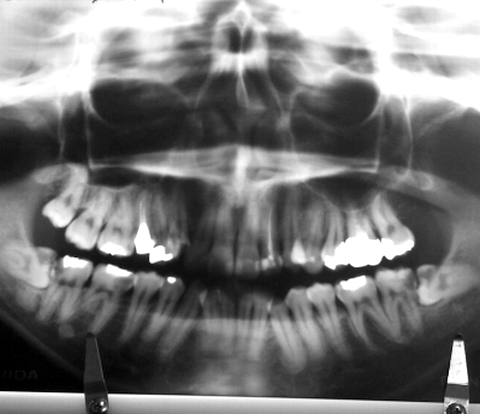

抜髄前のレントゲン写真をブログで公開していた。

左上3番と右上3番の他に左下3番と右下3番の歯が「みかん」は唇側転位した八重歯で、親知らずは右上8番が生えていて、左上8番は抜歯し、左下8番と右下8番は水平に生えて半埋覆していた。

左上2番、左上6番、右上5番の歯を「みかん」は抜髄済だった。

「みかん」は銀歯だらけで、左上6番に銀クラウンを被せ、左上7番、左上5番、左上4番、右上4番~右上6番、右下7番、右下6番、右下4番、左下6番に銀インレーを詰め、左上3番~右上2番には歯間隣接部にそれぞれレジン充填していた (反転画像を再反転、26歳時)。